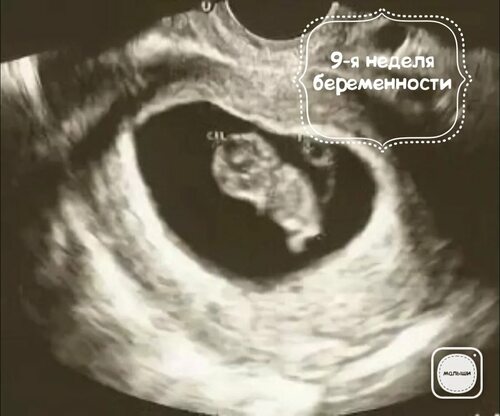

На 9-й неделе беременности многие мамы ждут возможности увидеть своего малыша на узи. В этой статье мы собрали много узи фотографий, чтобы вы могли узнать, как развивается ваш ребенок и что можно увидеть на узи на данном сроке.

Развитие ребенка на 9 неделе

На 9-й неделе беременности, ребенок продолжает активно расти и развиваться. Его органы и системы становятся все сложнее и функциональнее. На узи можно увидеть множество интересных деталей, которые свидетельствуют о развитии вашего малыша.